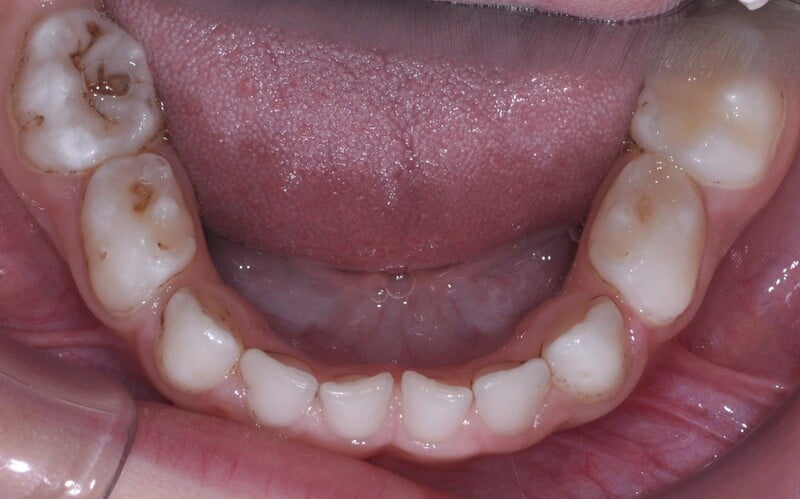

T.G., paciente do sexo masculino, com quatro anos de idade, dentição temporária completa, sem antecedentes médicos relevantes e com história prévia de falta de colaboração nas consultas de medicina dentária.

Foi realizado um exame clínico e radiológico inicial (fig. 1 a 3), tendo sido diagnosticada, entre outras lesões de cárie, uma lesão de cárie profunda com atingimento pulpar no segundo molar temporário inferior direito (fig. 3). Foi proposta a realização de uma pulpotomia com agregado trióxido mineral (MTA) e a colocação de uma coroa pré-formada. As várias possibilidades restauradoras foram apresentadas e discutidas com os pais, que decidiram optar pela colocação de uma coroa pré-formada de zircónia, por motivos estéticos.